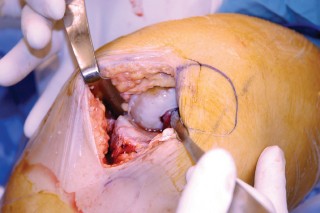

في جراحة استبدال مفصل الركبة الجزئي، يتم استبدال الغضروف والعظام التالفة في حجرة واحدة فقط من هذه الحجرات، عادةً الحجرة الإنسية، مع الحفاظ على الأربطة السليمة والأنسجة المحيطة.

إجراء جراحة استبدال مفصل الركبة الجزئي (UKA)

تُعد جراحة استبدال مفصل الركبة الجزئي إجراءً دقيقًا يتطلب مهارة وخبرة عالية. يتبع الأستاذ الدكتور محمد هطيف في صنعاء بروتوكولات جراحية صارمة لضمان أفضل النتائج لمرضاه.

1. التخطيط قبل الجراحة

-

القوالب المسبقة (Preoperative Templating):

يتم استخدام الأشعة السينية لتحديد حجم وموضع المكونات المزروعة بدقة قبل الجراحة.